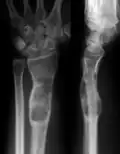

Abnormal bone growth such as shortening or thickening and deformity may be observed in patients of Ollier disease. These bone lesions are visible at birth using radiography but are usually not screened or examined for until clinical manifestations present during early childhood. However, some patients may exhibit no signs of any symptoms.[1] One study found thirteen to be the mean age of diagnosis in patients with Ollier disease. In an X-ray, there would normally be the presence of several homogeneous lesions of an oval or elongated shape with bone edges that are slightly thickened.[3] With age, these lesions may calcify and appear as diffusely minute spots or stippled. Fan-like septations or streaks would be indicative of the presence of several enchondromas. Early detection and consistent and repeated monitoring is important in order to prevent and treat any potential bone neoplasms.

X-ray showing calcified enchondromas localized in finger a 37-year-old patient affected with Ollier disease -

X-ray showing enchondromas localized in the lower part of the radius of a 37-year-old patient affected with Ollier disease -